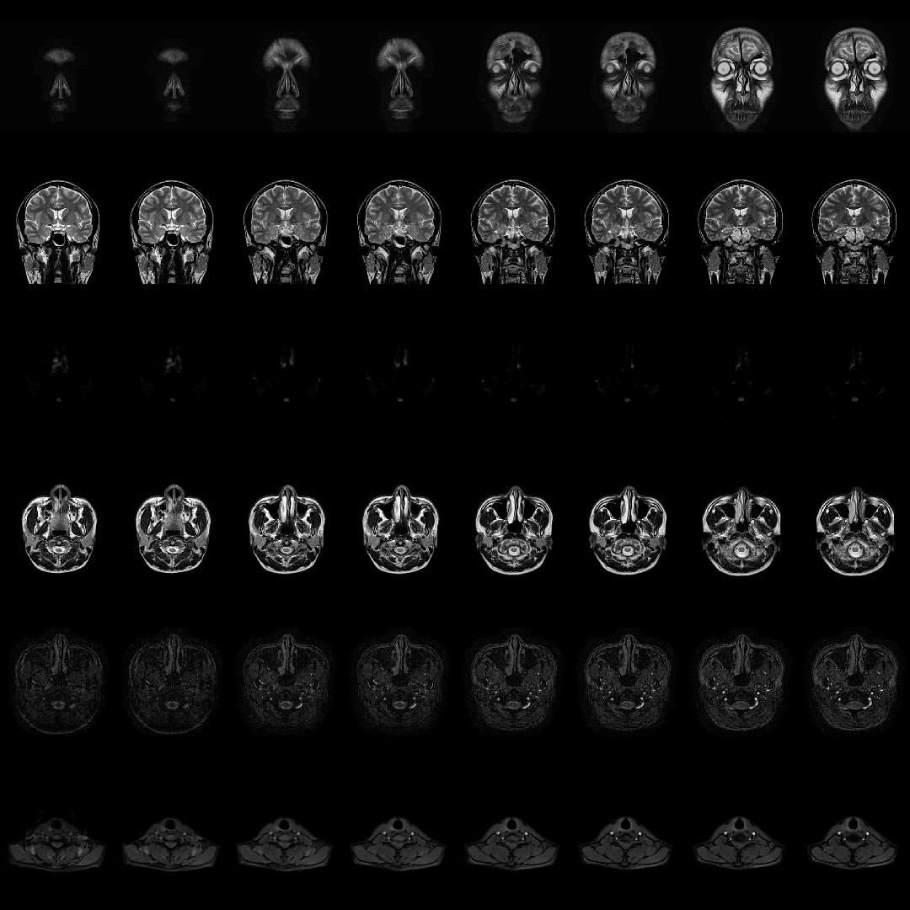

Visual using MRI sequence data(430 images) of my own brain got by myself at a medical facility(Date: 20 Jan 2021, Location: 35.672232571280645, 139.73366743753462).

I think that this NFT emphasizes the presence, existence and embodiment of human beings that cannot be duplicated and creates the concept of ma- terial intangibility and the situation that embodiment is not removed.